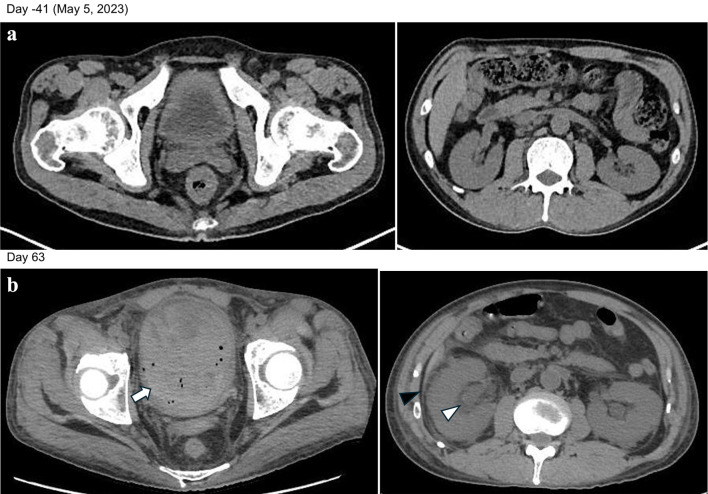

复发/难治性弥漫性大b细胞淋巴瘤(R/R DLBCLs)预后极差,目前没有确定的挽救性化疗。Polatuzumab, rituximab和苯达莫司汀联合治疗(Pola-BR)已被批准为R/R DLBCL的新治疗选择。最近,嵌合抗原受体t细胞治疗和双特异性抗体已经诱导了许多R/R DLBCL患者的长期缓解。然而,同种异体移植仍有可能治愈对上述治疗无反应的患者。虽然同种异体移植也会引起各种不良事件,但出血性膀胱炎是一种特别严重的并发症,需要有效的预防策略。在这里,我们报告了两例严重的BK病毒相关的出血性膀胱炎(BKV-HC),在早期复发的DLBCL的连续脐带血移植和清髓条件和Pola-BR治疗后发展。两例患者在接受多种挽救性治疗后均接受了Pola-BR,并在移植后发生了早发性BKV-HC,证明了Pola-BR和清髓调节的作用。我们分析了这两个病例之间的共同特征,以区分触发BKV-HC发病的因素和导致其严重程度的因素。基于两例患者临床病程的差异,我们提出了BKV-HC的预防策略,并确定了同种异体移植的R/R DLBCL患者Pola-BR的治疗策略。